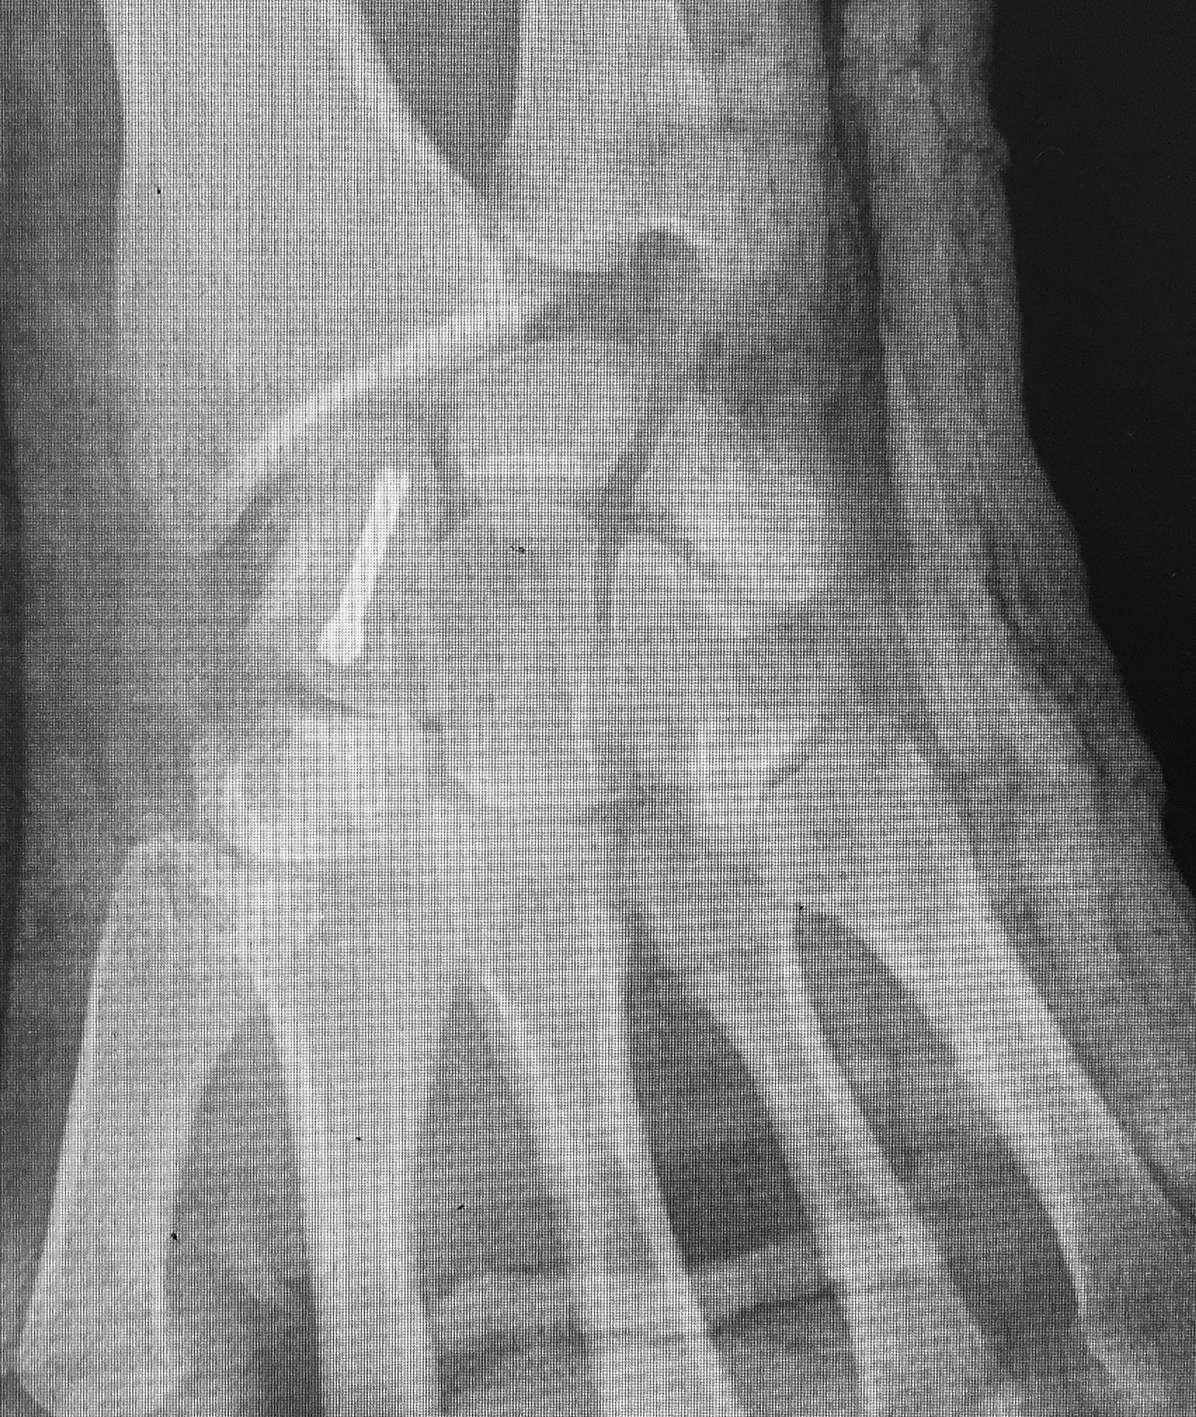

Efectuamos un abordaje volar dado que conserva la vascularización dorsal, permitía la visualización directa del foco, movilización de los polos y manejar la deformidad en joroba mediante el injerto trapezoidal (1)(11)(12). Nos centramos sobre el tendón palmar mayor, efectuando una incisión curvilínea dirigida hacia el tubérculo del escafoides. Se protegió la rama sensitiva cutánea del nervio radial y disecamos el plano superficial incidiendo la cápsula longitudinalmente sobre el eje del escafoides. Se reflejó la cápsula, se identificó el polo distal y proximal colocando dos agujas de Kirschner, a modo de joystick. Cureteamos el foco con una fresa (Figura 1). Dejando el escafoides, extrajimos un injerto cortico-esponjoso trapezoidal de cresta iliaca (Figura 2). Volviendo a la mano, distrajimos los fragmentos escafoideos y colocamos el injerto, con su base en situación volar, para extender el escafoides (1)(5)(12)(13). Colocamos otra aguja de Kirschner retrógrado como guía, y tras medir y mechar, colocamos un tornillo de compresión interfragmentaria (11), para proceder posteriormente a cerrar la cápsula y los planos superficiales. Se colocó una inmovilización con férula de yeso, incluyendo el primer dedo, que mantuvimos durante 4 semanas.

La evaluación de la movilidad mostró que 5 pacientes (29,4%) tenían la movilidad completa; 11 pacientes (64,7%) la conservaron entre el 75 y el 99 % y un paciente (5,9%) entre el 50 y el 74%. No encontramos asociación estadística entre la movilidad y el retraso terapéutico (p=0,241). (Figura 3) (Figura 4) (Figura 5) (Tabla 1) (Tabla 2).

Figura 3: Caso 9

a) Radiografia de perfil pre-opertaoria

b) TC pre-operatoria. Corte sagital

c) TC pre-operatoria. Corte coronal

d) Radiografías post-operatorias

e) Radiografía de frente, 33 meses seguimiento, pseuodartrosis persistente

f) Radiografía de frente, 33 meses seguimiento, pseuodartrosis persistente

g) 33 meses de seguimiento, flexión de muñeca

h) Extensión de muñeca